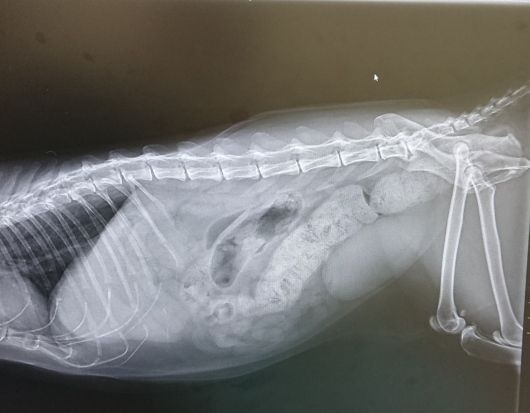

「気持ち悪いですニャ。」

「早く何とかして下さいニャ。」

原因は、どうやら便秘

先生に出口付近の便を掻き出していただきました。

便に血も混じっており、急性大腸炎を発症した模様。

脱水症状も起こしていたので、補液と吐き気止め、抗生剤を処方していただきました。

帰宅後も、石のような硬さの便を少し出したので、注意しながら様子を見ています。